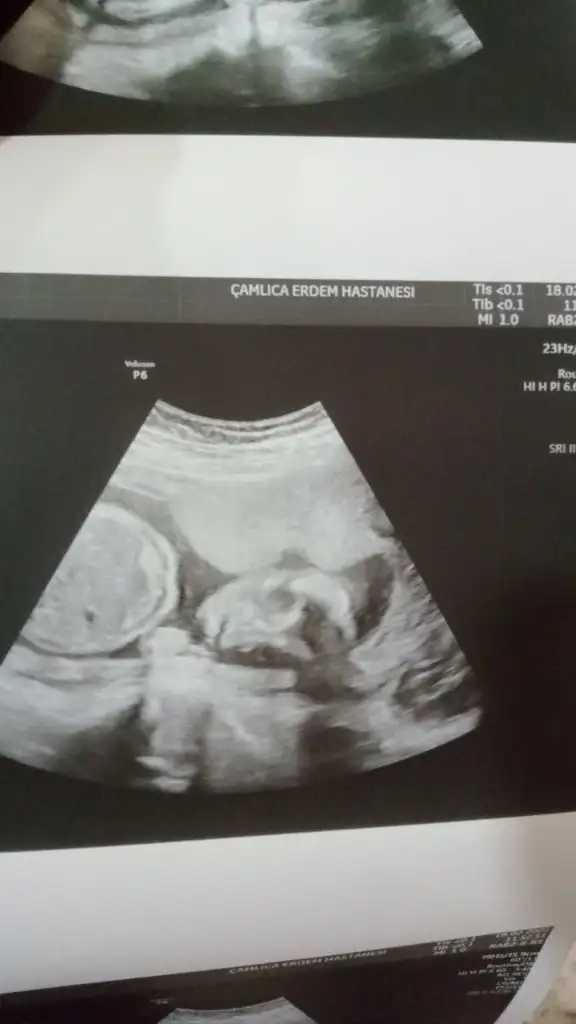

Ay benim en sevdiğim çizgi filmdi casperBuda benım bebısın suratı teyzeleriasırı belli degil ama annelik iç güdüsüyle görebldigim kadarı bıle muazzam geliyor peki eşimin görünce yorumu " aynı sevimli hayalet casper " bu adam beni öldürecek